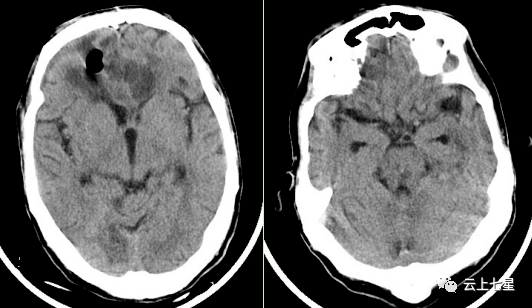

道是无形却有形于无形处成万形气颅精准治疗一例